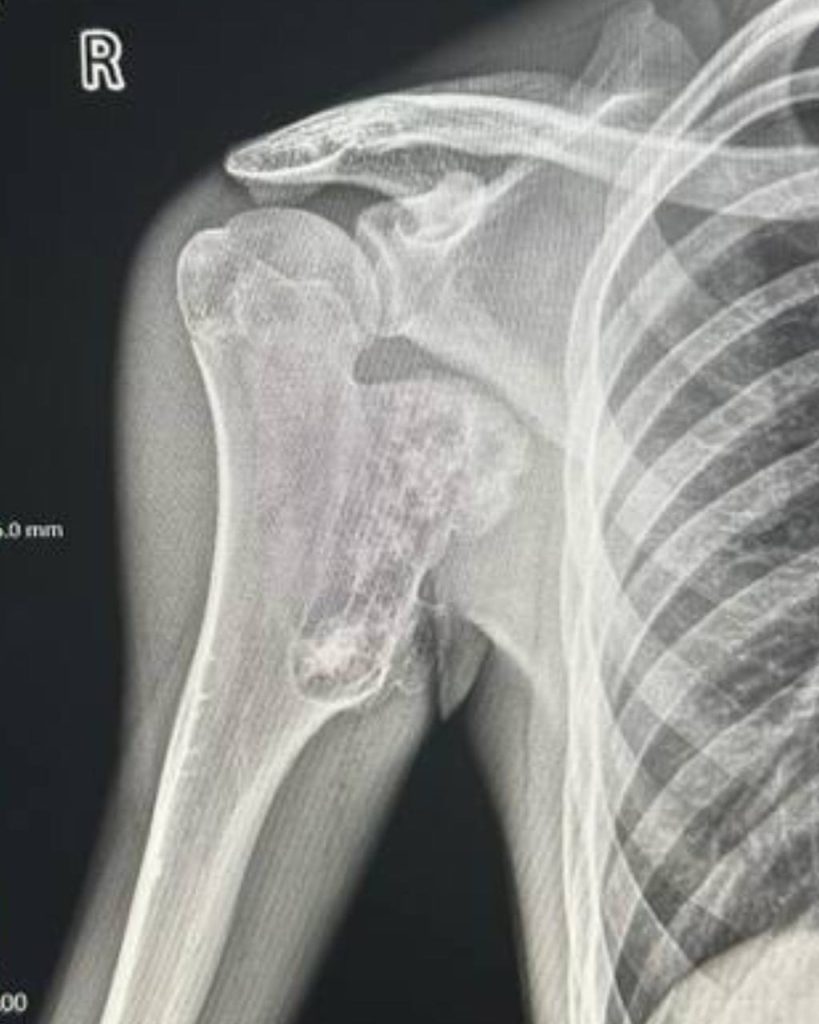

Клінічний випадок. Пацієнт звернувся до нас зі скаргами на утворення у верхній третині плеча, яке заважало притиснути руку до тулуба, а також на оніміння пальців кисті. Після клінічного огляду та рентгенологічного обстеження утворення було розцінене як остеохондрома.

Було виконано крайову резекцію плечової кістки з подальшим накістковим металоостеосинтезом, що дозволило усунути проблему та зберегти функцію кінцівки.